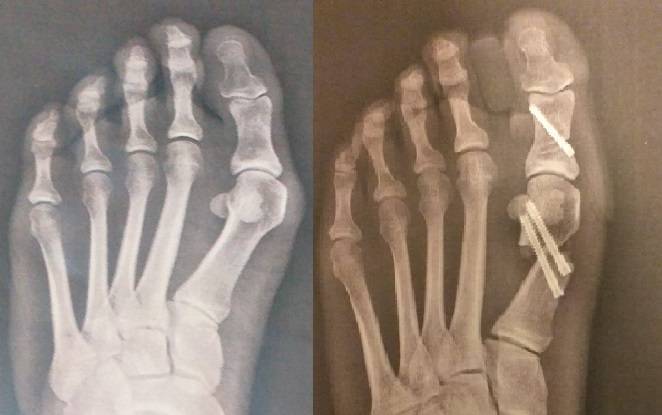

Cirugía percutánea de pies antes y después

Para realizar dicha corrección utilizamos osteotomías correctivas y las estabilizamos con tornillos de 3 a 3.5 mm canulados, podemos observar las fotos del pie y radiografias antes y despues